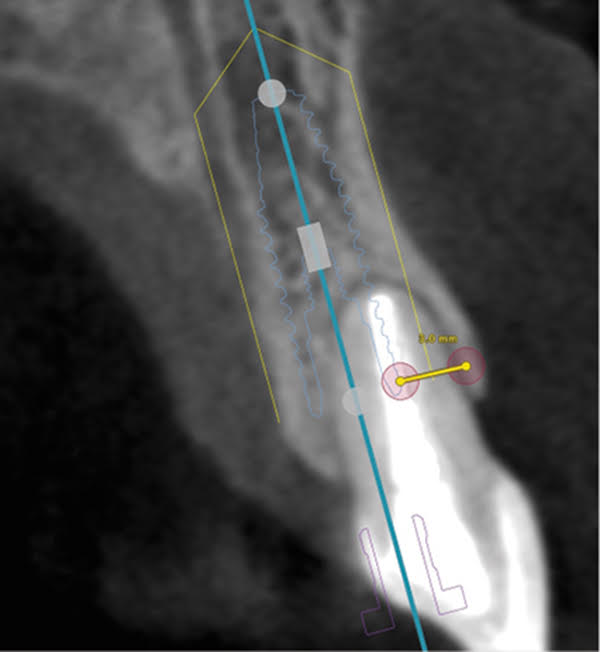

The patient, a healthy 45-year-old nonsmoking woman (American Society of Anesthesiologists [ASA] II), presented with a failed maxillary central incisor due to severe internal-external root resorption (Figure 1). She had a high esthetic risk profile based on 12 presenting esthetic risk factors (key No. 1), including a high lip line, high esthetic expectations, and adjacent teeth that had been restored (Figure 2).Site-specific CBCT (Carestream CS 9300, Carestream Dental, carestream.com) noted a thick intact buccal plate and a class 1 sagittal root position (Figure 3 and Figure 4). Preplanning with a bone-level 4.1-mm diameter x 14-mm long implant (Straumann Bone Level Roxolid® SLActive, Straumann, straumann.com) assured a 3-mm buccal gap upon placement and a screw-retained position (key No. 2). Prior to placement, intact buccal and palatal walls were confirmed. Figure 5 shows palatal wall placement of the implant after minimally traumatic flapless tooth extraction. An anatomically correct surgical guide template was used to assure a screw-retained position and correct vertical depth of approximately 4 mm from the mid-buccal apical extent of the guide template, which correlated to 1 mm apical of the intact buccal plate (key Nos. 3 through 5). The two-unit (8-9x cantilever) fixed provisional was recemented post-surgery. The 3-mm buccal gap was grafted tightly with a low-substitution DBBM (Bio-Oss®, Geistlich Pharma, geistlich-na.com) (key No. 6), and a pouch was created with a Buser membrane instrument (Hu-Friedy, hu-friedy.com) from line angle to line angle as a mini full-thickness flap to the mucogingival border to accept a connective tissue graft (Figure 6). The connective tissue graft, 1-mm thick x 12-mm long x 7-mm wide (Figure 7), was harvested from the palate (key No. 7).

Fig 3. Pretreatment site-specific CBCT showing thick intact buccal plate and class 1 sagittal root position. Preplanning with a bone-level 4.1-mm diameter implant assured a 3-mm buccal gap upon placement and a screw-retained position.

Figure 3

Fig 4. Pretreatment site-specific CBCT showing thick intact buccal plate and class 1 sagittal root position. Preplanning with a bone-level 4.1-mm diameter implant assured a 3-mm buccal gap upon placement and a screw-retained position.

Figure 4